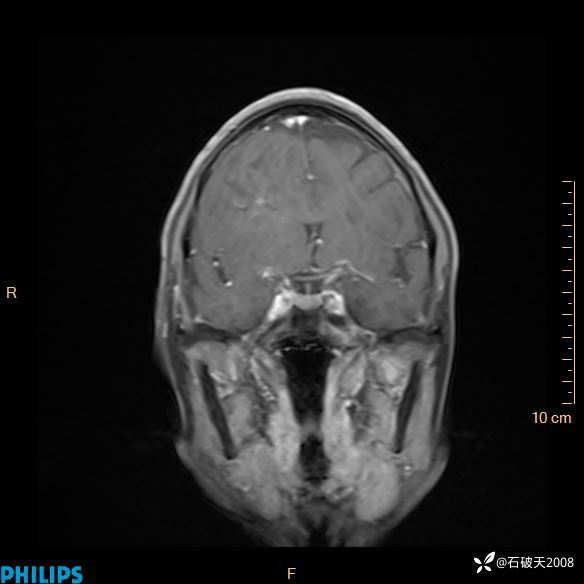

2024.2.21MR

增强冠状位